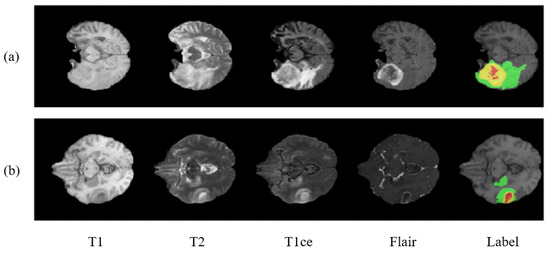

2. Datasets

- Enhancing tumor.

- Necrosis and non-enhancing tumor.

- Edema.

- Healthy tissue.